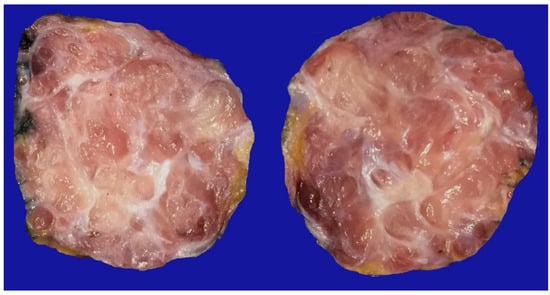

A total of 776 cases of endometriosis were collected between the two institutions that participated in the study, in different anatomical sites (Table 1, Scheme 1), of which 54 presented with a myxoid stroma >50% with respect to the cellularity of the samples and represented 6.95% of the total endometriosis examined, with the following locations: omentum (4/20), ileum (2/4), ovary (14/216), parametria (2/9), soft tissues (28/235), salpingus (3/77), and bladder (1/4). The clinical records of these patients were consulted, and the common denominator was that these women were in the surgical (41/57) or physiological (7/39) puerperium during 24 h postpartum to 6 months after said event. Macroscopically, two different lesions were observed: the first one, which is the most frequent, presents as a non-encapsulated lesion with pushing edges of a fibromyxoid appearance; the second and less frequent, is a well-defined lesion, partially or totally encapsulated, with a shiny cut surface, gelatinous in appearance, multilobed, and light brown to brown in color with focal areas of recent and old hemorrhage; these lobes are separated by fibrous septa (Figure 1). Histologically, it was found that in all the samples evaluated, at least 50% of myxoid stroma with some fine connective tissue septa with the proliferation of stromal cells (Figure 2A) presented the following four variants in their shape: (1) Epithelioid stromal cells of wide eosinophilic cytoplasm with round small nuclei (Figure 2B), (2) pseudolipoblast-type stromal cells with moderate cytoplasm, multivacuolated in their cytoplasm that can present eosinophils or clear cytoplasm, with central nuclei of granular chromatin (Figure 2C), (3) “pseudosignet ring” stromal cells with the nucleus and cytoplasm rejected to the periphery giving the described appearance (Figure 2D), and (4) immersed spindle cells with discrete nuclei (Figure 2E). Among these cells, the epithelial component was observed, with tubules ranging from small to large cystic dilations of the gland that present a layer of low cubic to cylindrical epithelium, generally with an atrophic appearance (Figure 2F). Hyaline globules were found in the glandular lumens (Figure 2G). The extracellular matrix showed a composition of glycosaminoglycans in 100% of the cases by staining present for AA (Figure 3A–C), but without staining for PAS; however, the latter stained on proteinaceous globular material in the lumen of the endometrial glands (Figure 3D). Immunohistochemistry for CD10 was positive in 100% of the stromal cells with a mild to moderate reaction in the cytoplasm and membrane with a decidual appearance (Figure 4A,B). The ER and PR showed nuclear expressions in 100% of cases, with greater intensity in the ER (Figure 4C) than PR (Figure 4D); both hormone receptors were expressed on the endometrial epithelial and stromal cells. The cases of myxoid endometriosis examined did not present cytological atypia, suggesting any precursor lesion of epithelial or stromal origin.

Figure 1.

Gross image of an abdominal tumor corresponding to myxoid endometriosis. Note the presence of fibrous septa framing the myxoid areas.

Immunohistochemistry is a powerful tool that allows for differentiating between different histotypes. However, for individuals who are poorly trained in this technique or those with little experience, immunohistochemistry can cause diagnostic confusion, especially when the necessary clinical data are not available. When approaching a tumor like the one presented in Figure 1, the lack of suspicion of myxoid endometriosis, ignoring the histological criteria that we proposed, can draw a thin line between benignity or malignancy diagnosis. Immunohistochemistry should only be used in the case of a suspected diagnosis, and only pathologists can decide on its use, which is why, although the study and review are of general utility, the approach directed to pathologists is vital for the recognition of this entity.